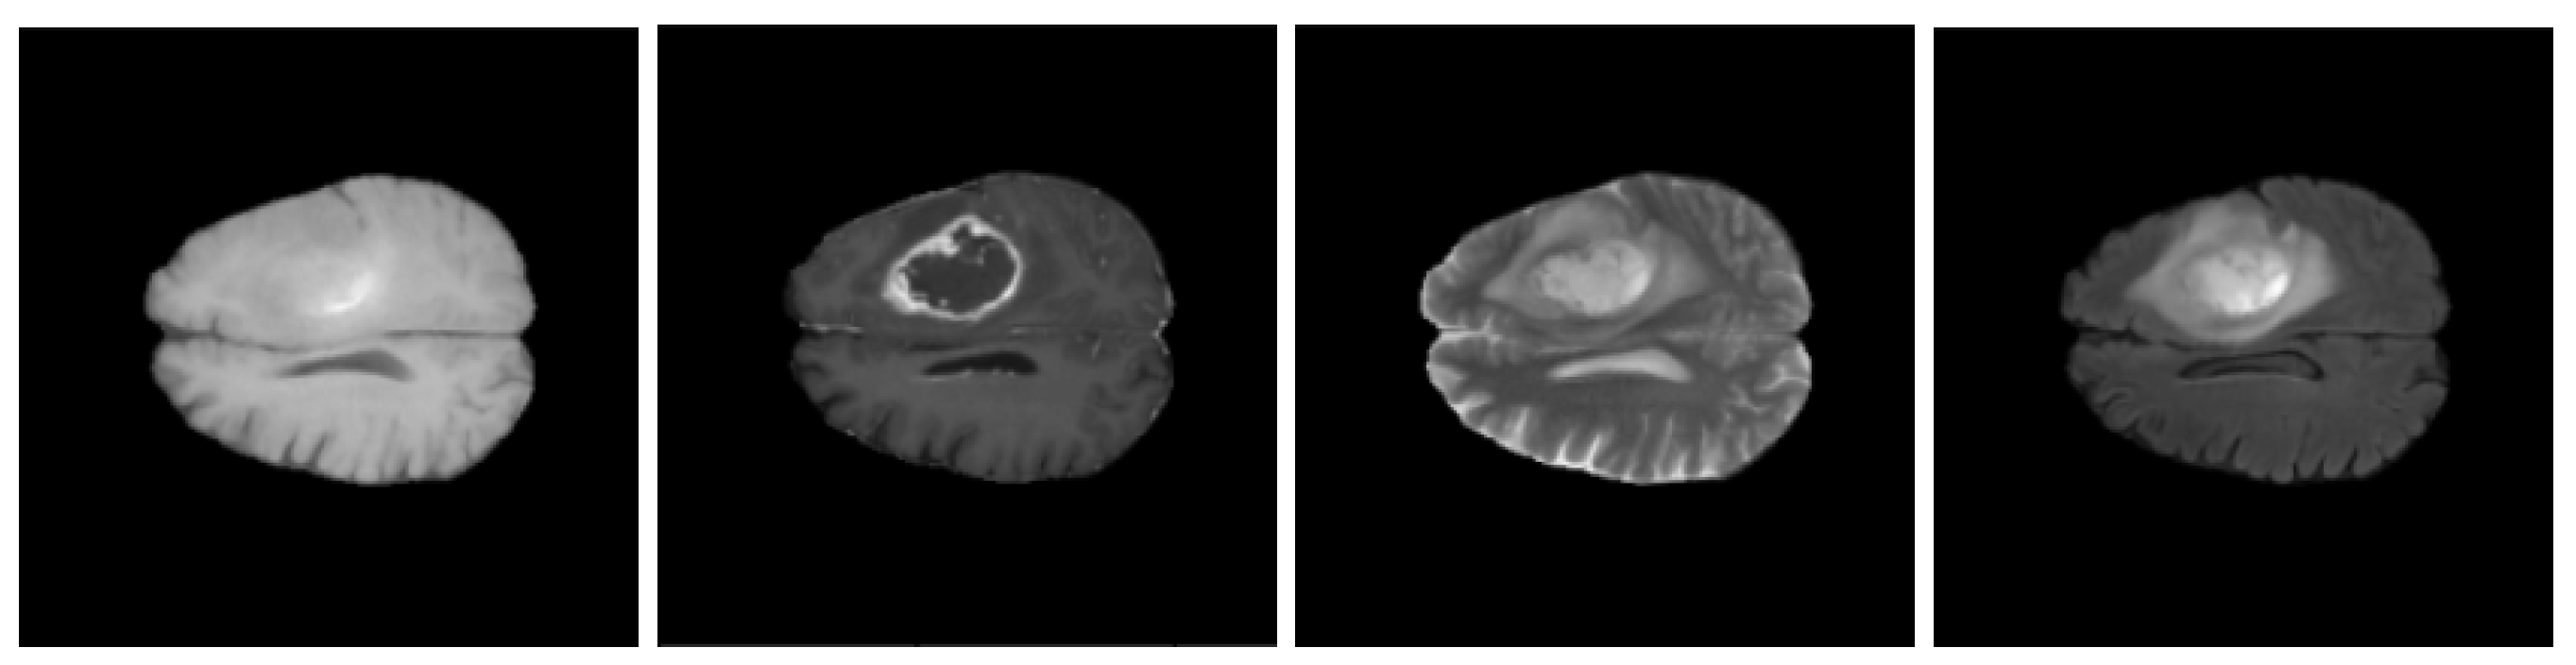

3.1. BraTS 2020 Dataset

7.1. Visual Error Analysis